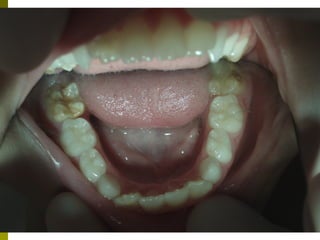

Τερηδόνα βρεφικής και νηπιακής ηλικίας

 Πρόσφατη επιδημιολογική μελέτη σε παιδιά

ηλικίας 5 ετών στην Ελλάδα, συχνότητα

εμφάνισης 43% με δείκτη dmft 1,8

 Η κατανομή των βλαβών είναι ανισομερώς

κατανεμημένη, με ένα ποσοστό 10-15%

των παιδιών να συγκεντρώνουν το 50%

των βλαβών